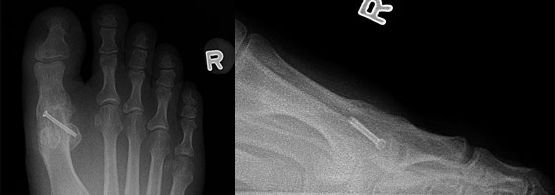

Query: Pain in Hallux Interphalangeal Joint

I have a 52 year old male patient who had a 1st MTPJ fusion about 18 months ago and, now has pain in his hallux interphalangeal joint.

Pain in 1st hallux interphalangeal joint S/P MTPJ fusion |

He tried an OTC orthotic with a met pad, which "did nothing." Any suggestions?

Jordan Sheff, DPM, Newport, RI